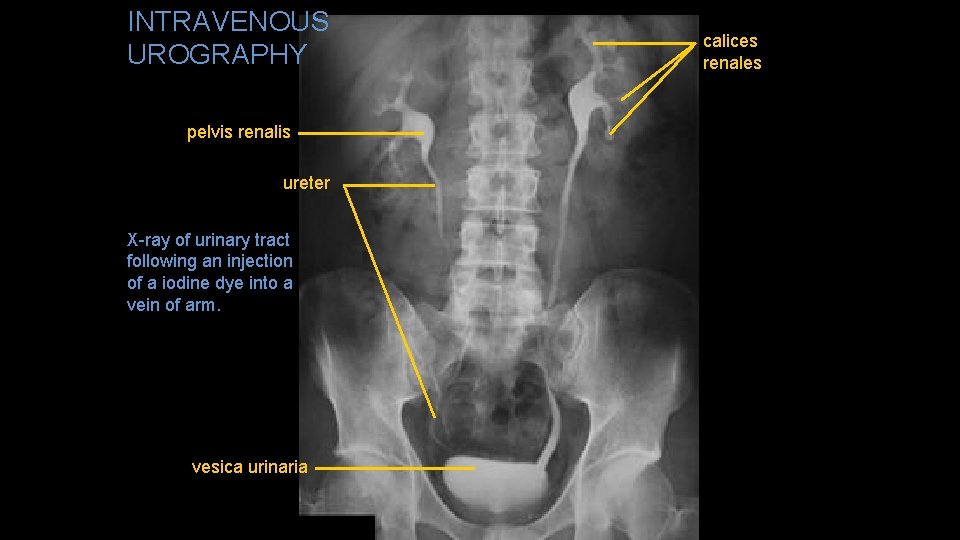

INTRAVENOUS UROGRAPHY pelvis renalis ureter X-ray of urinary tract following an injection of a iodine dye into a vein of arm. vesica urinaria calices renales